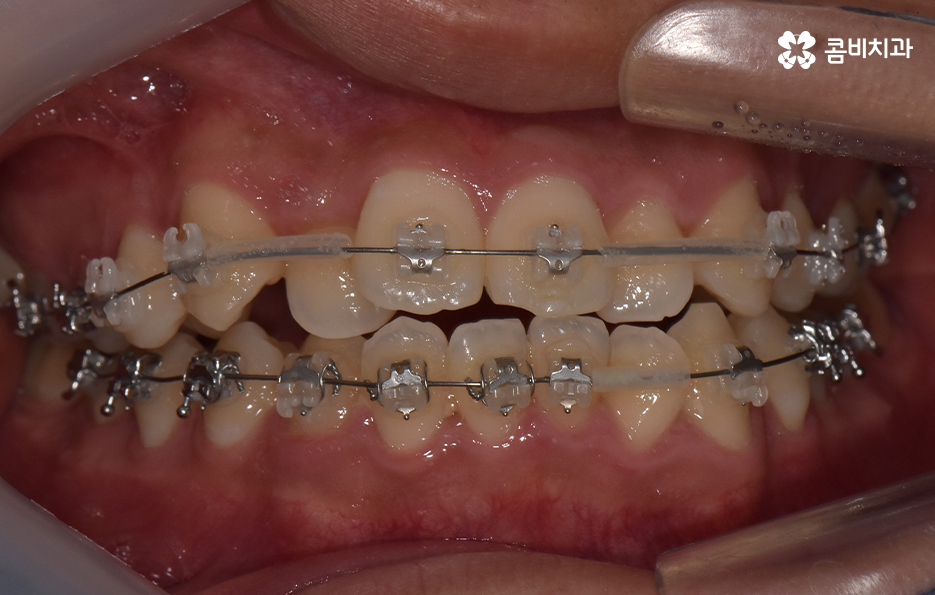

오늘 포스팅에서 보여지는 사진에서는 비발치 교정으로 덧니 교정이 가능했던 사례입니다. 덧니 교정 사례에서 발치교정 케이스는 흔한 치료 방법이긴 하지만 발치에 대한 판단은 치열만이 아니라 골격과 얼굴형을 종합적으로 고려하여 판단하고 치아를 얼마나 이동시켜야 할지 예측하여 판단하기 때문에 3D CT 등의 첨단 장비를 통한 검진과 경험 많은 교정 전문의와 충분히 상의하고 결정해야 합니다

종합하면 발치교정의 필요성은 얼굴과의 조화, 골격 그리고 교합 등을 전체적으로 고려하여 판단하기 때문에 각 환자분들이 필요한 치아의 이동 정도를 정확히 예측하고 필요한 치아 이동 공간을 확보함에 있어서 발치교정이 적합할지 아니면 비발치적인 방법으로도 치아 이동 공간이 확보 가능한지 따져보고 있으며 발치교정이 아니더라도 치간삭제, 악궁확장, 어금니 후방이동과 같은 방법으로 공간 확보가 가능하기 때문에 각 환자분들에게 적합한 1:1 맞춤형 치료가 진행되고 있어요